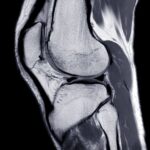

Czym jest woda w kolanie i skąd się bierze?

Woda w kolanie to potoczny termin odnoszący się do nadmiaru płynu maziowego, który gromadzi się w torebce stawowej. Zjawisko to powstaje w wyniku różnych czynników, w tym stanów zapalnych stawu kolanowego. Przyczyny gromadzenia się płynu w kolanie mogą obejmować urazy mechaniczne oraz nadmierne obciążenie stawu, co prowadzi do zwiększonej produkcji płynu przez błonę maziową.

W związku z tym, kolano staje się opuchnięte, a pacjenci często skarżą się na ból, który znacząco utrudnia poruszanie się. Stany zapalne stawu kolanowego, jak zapalenie kaletki przedrzepkowej czy dna moczanowa, mogą być głównymi przyczynami wody w kolanie. Warto zwrócić uwagę na objawy towarzyszące, ponieważ mogą one sugerować poważniejsze schorzenia.